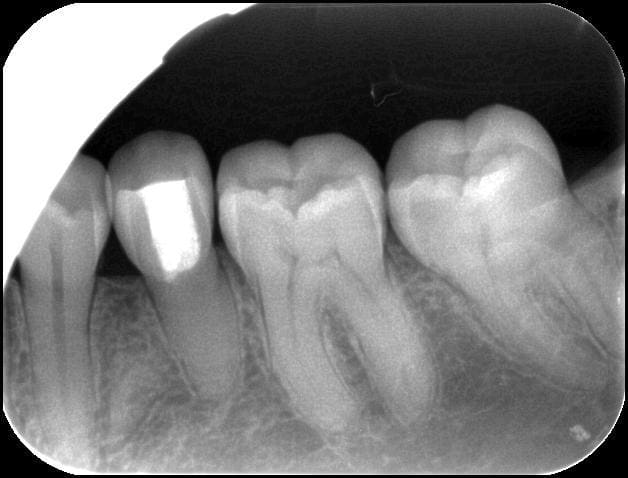

La patiente de 31 ans ne se souvient plus

La 35/18 a eu une pulpo ? (ou artefact contrast?).